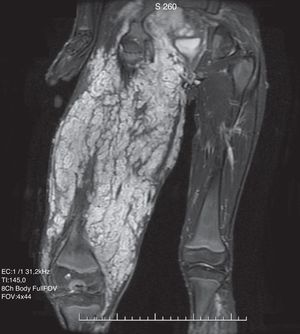

El neurofibroma plexiforme tiene una apariencia patognomónica. Se observa como una nodularidad difusa de todo el recorrido del nervio y sus ramas, con una hiperintensidad similar al agua en las secuencias ponderadas en T2. Los de gran volumen reemplazan el tejido adiposo creando una apariencia en «panal». Clínicamente se manifiestan por elefantiasis neuromatosa37–39 (fig. 6).

Niño de 14 años, con antecedente de neurofibromatosis tipo I. Secuencia SSFSE ponderada en T2 en el plano coronal del muslo, en la que se observa una formación voluminosa en las partes blandas del muslo, con alta intensidad de señal, polilobulada, con múltiples septos. La biopsia demostró un neurofibroma plexiforme del nervio ciático.